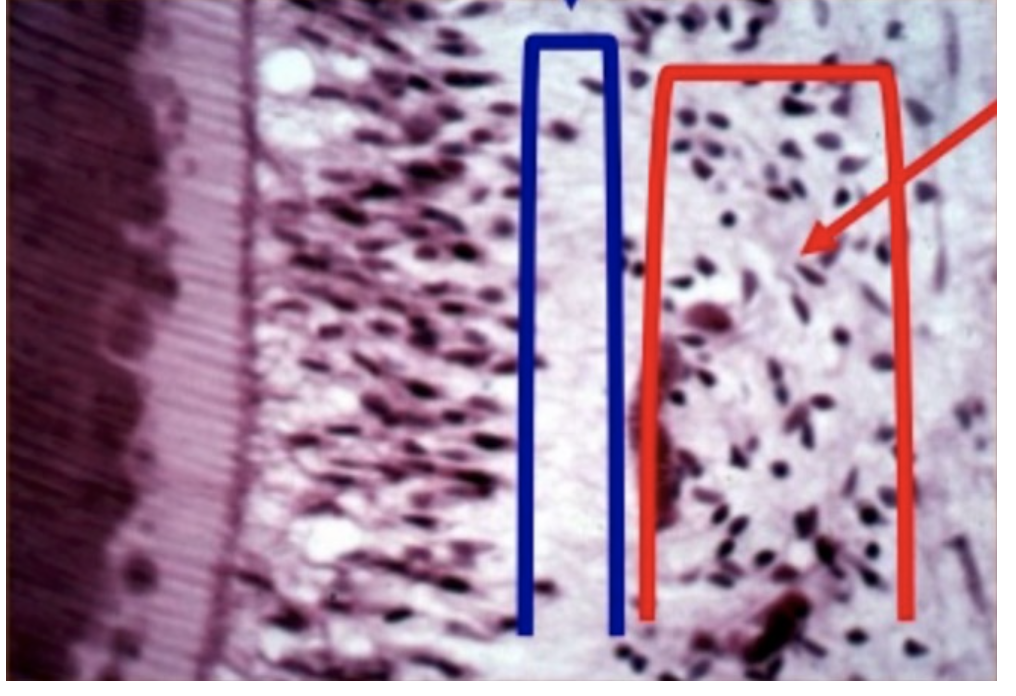

Histologic Zones of Pulp

A

Predentin: not mineralized

Odontoblastic layer: where nuclei are laying down dentin

Cell free zone of Weil: 0 nuclei/no cells

Cell-rich zone

Pulp core